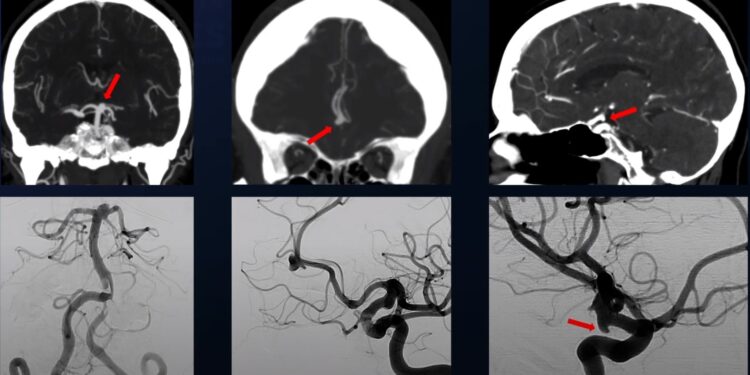

Falë zhvillimit të teknologjive mjekësore si skaneri, rezonanca magnetike dhe angiografia, aneurizmat tashmë zbulohen gjithnjë e më shpesh përpara se të këputen. Kjo lejon një vlerësim të hershëm të madhësisë dhe formës së tyre, duke ndihmuar në parashikimin e rrezikut të rupturës. Aneurizmat që janë më të mëdha se pesë milimetra, veçanërisht ato të vendosura në arteriet kryesore të trurit si arteria cerebrale e mesme, arteria komunikuese anteriore dhe arteria bazilare, konsiderohen më të rrezikshme për këputje.

Në rastin kur një aneurizëm diagnostikohet, trajtimi ka për qëllim ta përjashtojë atë nga qarkullimi i gjakut. Kjo mund të bëhet në mënyrë endovaskulare, përmes një kateteri që kalon nëpër rrjetin e enëve të gjakut, deri në tru, ku më pas aneurizma mbushet me spirale platini që e mbyllin atë. Kjo metodë është më e rehatshme për pacientin, sidomos në rastet kur aneurizma nuk është këputur ende. Por kur ka ndodhur një gjakderdhje e madhe, ndërhyrja kirurgjikale është më e përshtatshme, sepse përveç izolimit të aneurizmës, lejon edhe pastrimin e gjakut të derdhur, çka ul presionin në tru.